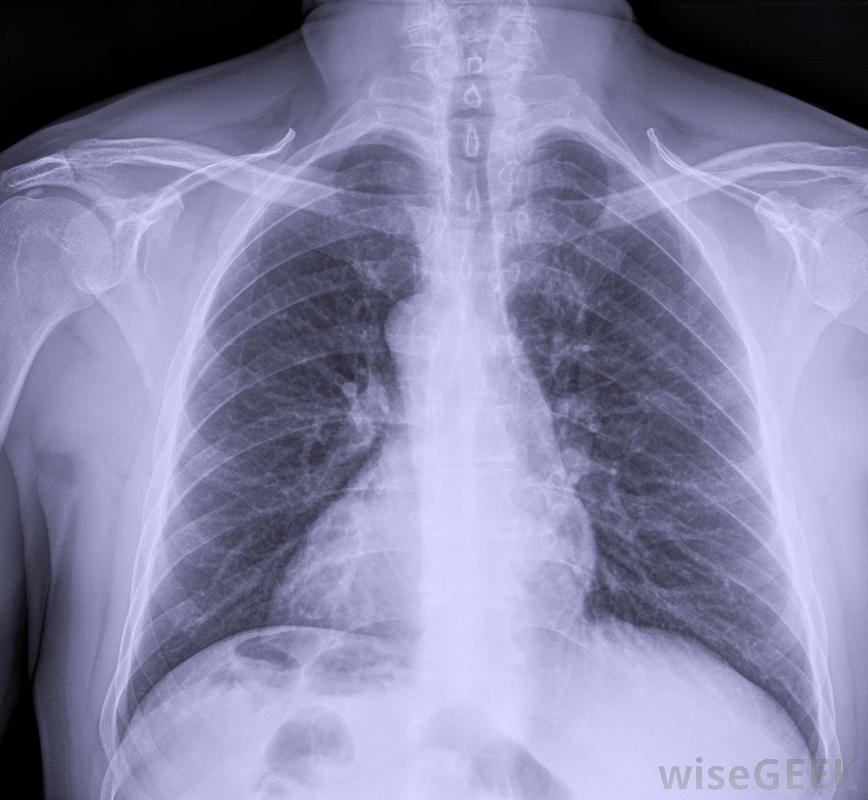

入境体检可能需要进行胸部X光检查。建议计划完成移民的申请人体检是预先为评估做准备的。申请人应该准备好所有必要的文件和疫苗接种的证明。申请人应该研究移民过程和任何可能被问到的问题,以减轻这种经历的压力

肺结核的皮肤测试通常是移民体检的一部分。移民体检还将确定申请人是否需要医疗检查可以在进行此类检测的特殊诊所进行。通常被称为移民诊所,互联网搜索可以提供进行检测的地点。除了疾病,检测还将显示血液中存在非法物质和麻醉品为确定申请人的健康状况和无传染病,将从个人身上抽取血液进行实验室检测,并对血液进行梅毒和人类免疫缺陷病毒(HIV)的存在进行筛查,从而获得免疫力缺乏综合症(AIDS)是严重的公共卫生问题。通常,这些测试将对15岁以上的申请人进行,或者任何被怀疑感染了这两种疾病的儿童。结合移民体检,美国公共卫生官员要求所有申请人接种最新和最新的疫苗。疫苗接种的类型可能因申请人的年龄而异。这些指南由美国政府确定。申请人还将接受肺结核的皮肤测试,结果通常在几天内就知道了如果需要做胸部x光检查,申请人必须在规定的时间内完成一次。在所有的检查和评估完成后,移民医生将为申请人填写一份表格。该表格被称为I 693,将显示所有的结果通常都要密封在一个信封里。表格要交给美国移民局。